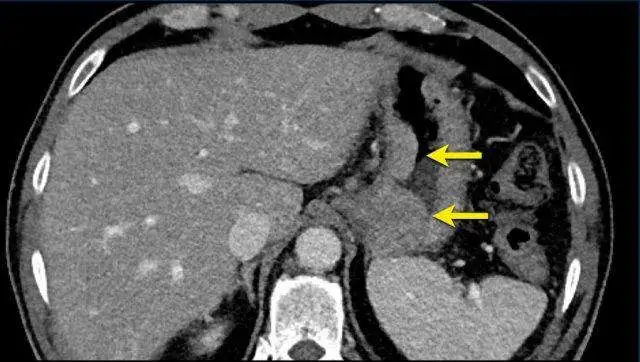

一名61岁的男性,患有胃癌并淋巴结转移,腹部CT图像显示胃壁可见一个比较大的分叶状肿瘤,

在后续检查中,肿瘤位置、形态会随呼吸及胃蠕动发生改变,可重复测量性较差,

因此,这种移动性肿瘤不适合选作靶病灶,但可以作为非靶病灶来评估。

上一张图像同一患者,在CT图像的其他层面,可以看到肿大的淋巴结,这更适合选做靶病灶(黄箭)。